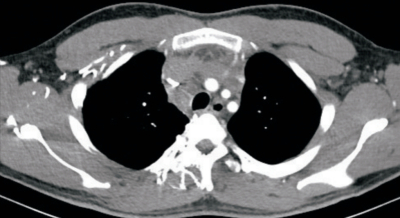

21歳の男性。1か月前からの顔面浮腫、労作時の呼吸困難を主訴に来院した。既往歴に特記すべきことはない。顔面と頸部および上肢の浮腫を認め、胸壁静脈の怒張を認めた。経皮的針生検により縦隔原発精上皮腫と診断された。胸部造影CTを別に示す。

この患者の症状はどの部位の狭窄によるものか。

a. 上大静脈